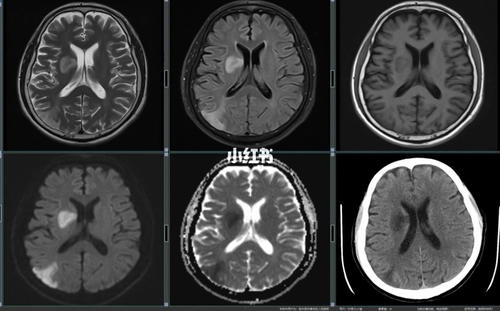

多发脑梗灶什么意思

脑梗灶是什么意思

脑内多发腔隙性脑梗塞灶

多发腔隙性脑梗死是什么意思?-看病网

脑内多发缺血灶是什么意思

检查医生说是脑内多发缺血灶,想问一下严重吗?

脑内多发缺血灶是怎么回事?

脑内多发性缺血灶是什么病?

在医院做脑部核磁共振检查出来是,脑内多发腔隙性脑梗死及缺血灶

脑内多发缺血灶与腔隙性脑梗都是脑梗吗?